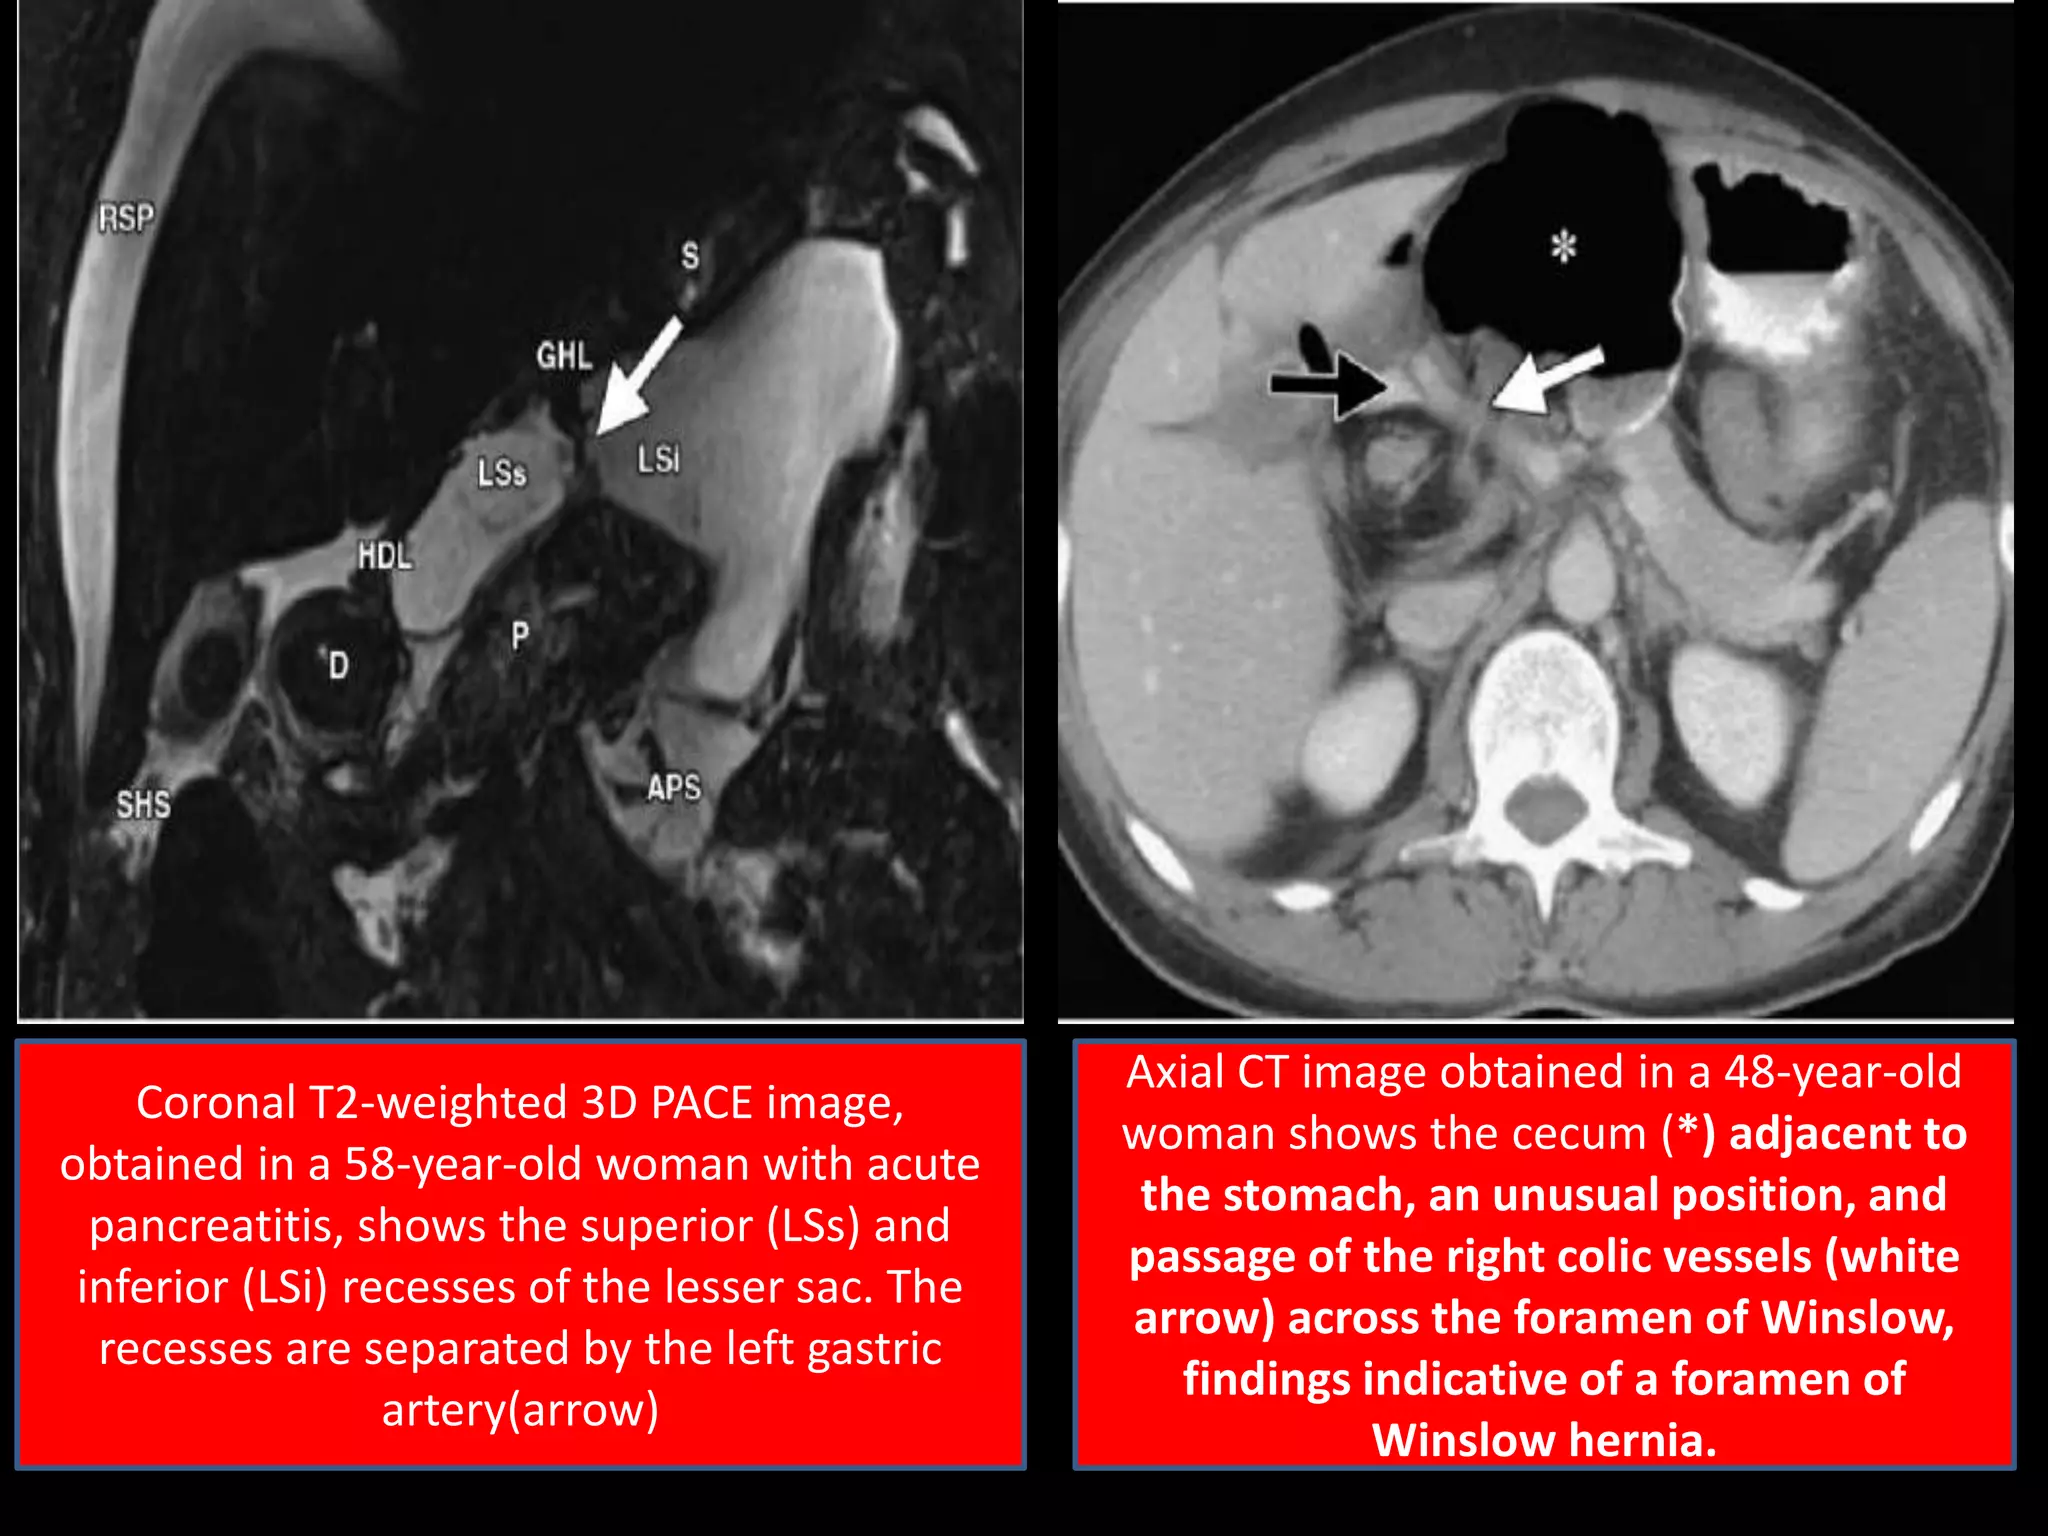

Coronal T2-weighted 3D PACE image,

obtained in a 58-year-old woman with acute

pancreatitis, shows the superior (LSs) and

inferior (LSi) recesses of the lesser sac. The

recesses are separated by the left gastric

artery(arrow)

Axial CT image obtained in a 48-year-old

woman shows the cecum (*) adjacent to

the stomach, an unusual position, and

passage of the right colic vessels (white

arrow) across the foramen of Winslow,

findings indicative of a foramen of

Winslow hernia.